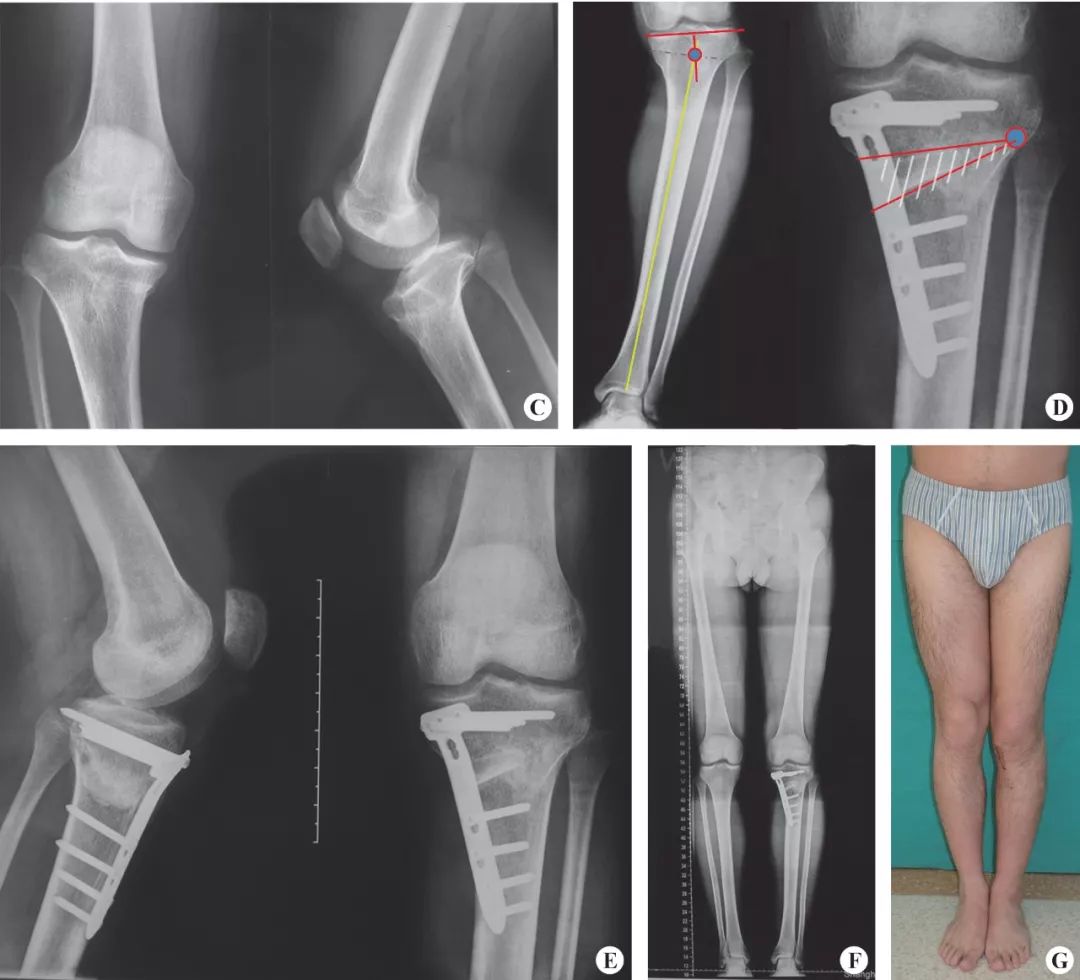

A 术前双下肢正面观;B 术前双下肢全长片;C 术前膝关节片;D 术前畸形分解确定CORA(蓝色圆圈),并草拟开口截骨区(白色斜线区);E 术后膝关节片,开口截骨的皮质骨铰链位置位于CORA的tBL上;F术后双下肢全长片;G术后外观